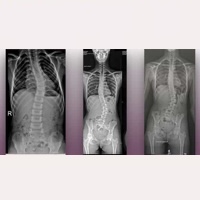

Online Patient Sessions: Arnold-Chiari I, Idiopathic Syringomyelia, Idiopathic Scoliosis and other associated conditions. Read more » 13 October, 2025

Favourable evolution of a case with Arnold-Chiari I Syndrome and Idiopathic Syringomyelia, 7 years after the application of the Filum System® Read more » 04 July, 2025